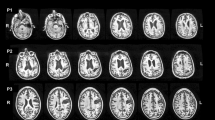

The linear regression models, however, showed that among all of these grey and white matter structures, only the thalamus (F(1,97) = 4.513, p = 0.036, ηp2 = 0.05), Heschl gyrus (F(1,97) = 4.788, p = 0.031, ηp2 = 0.05) and fornix (F(1,97) = 4.247, p = 0.042, ηp2 = 0.04) could be attributable to the personal neglect symptoms. None of the other tracts and lesions were statistically significant after controlling for extraneous clinical and neuropsychological deficits (all p > 0.07, ηp2 < 0.02) (Fig. 1).

Grey and white matter structures damaged in personal neglect. a The lesions from the voxel lesion symptom mapping (Lesymap) and the comparison with the null model (i.e. only clinical variables). Numbers refer to the Z in the MNI coordinates. b Thalamus (X = 18; Y = 17; Z = 5); in the square, details of the thalamic cluster of lesion are shown. c Lesions in the gyrus of Heschl (X = 46; Y = 12; Z = 8). Colour bar represents the p statistics resulting from the lesion analyses. 10-FWER: p values are calculated from the tenth highest t value and familywise error corrected. d Medial and lateral view of the fornix. e Antero-medial view of the network of personal neglect as resulting from the comparisons of the regression models and including the gyrus of Heschl (green), thalamus (yellow), and fornix (blue). L left, R right

Finally, the model that takes into account these three structures explains the symptoms better than clinical variables alone (F(3, 98) = 3.087, p = 0.031, ηp2 = 0.09).